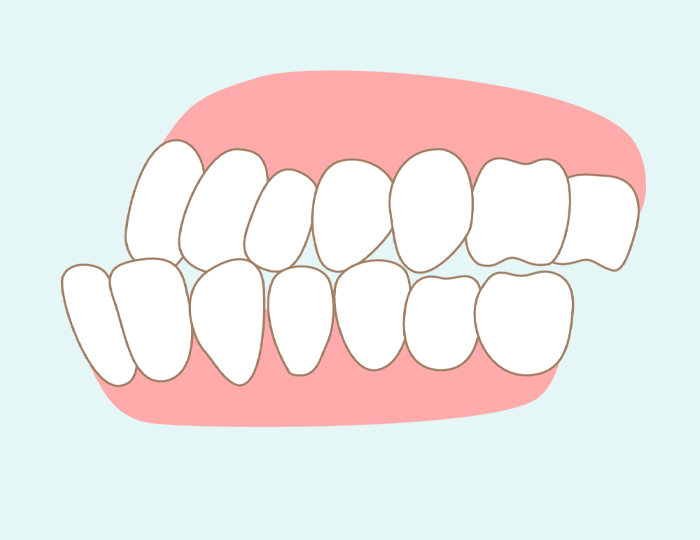

乱ぐい歯

乱ぐい歯は、顎が小さいために歯が並ぶスペースが狭く、歯と歯が重なり合ってデコボコに並んでいる状態です。叢生(そうせい)や八重歯とも呼ばれています。永久歯は乳歯よりもサイズが大きいため、顎が小さく乳歯と乳歯の間に隙間がない状態だと、生え変わった後に歯並びが乱ぐい歯となってしまいます。

なお、顎の骨の成長は、舌が上顎の骨を押すことによって促されます。例えば、お子さまがぽかんとお口を開けて口呼吸をしていると、舌を置くポジションも低くなり、上顎へ刺激が伝わりません。その結果、顎が小さいままで発育が止まってしまうのです。上顎が十分に成長しないと副鼻腔の成長も妨げられるため、鼻詰まりや免疫機能の低下にもつながっていきます。